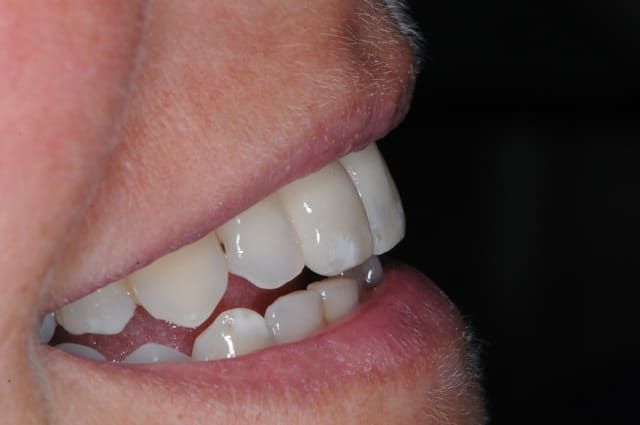

Bah moi je le tente....

J'ai fait un cas similaire tout récemment.

Je le mettrais plus tard sur mon book quand j'aurai fait la découverture . Je veux faire 2 publi par semaine alors je vais pas tirer toutes les cartouches tout de suite.

Je poste le cas en avant premiere ici.

C'est tout frais du mois dernier.